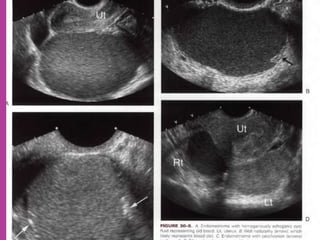

Ovarian Endometriomaa

 Study ofnormal uterus and adnexa – with aim to have clear image of normal myometrium, endometrium , ovary and follicles within the ovary.  Myoma—to differentiate myoma from adenomyoma.localization of myoma—sub serous/ intra mural or sub mucous.  Adenomyosis---accurate diagnosis.  Congenital uterovaginal anomalies— bicornuate, septate,subseptate , unicornuate, didelphys ,rudimentary horn and vaginal atrasia etc

 MRI ismost sensitive for diagnosis of Adenomyosis.  MRI Is more accurate and informative in diagnosis of congenital malformation of genito-urinary tract.  Retroparitoneal lymph node > 1cm can be identified so also such small deposits on bowel / bladder liver can be identified in cases of cancers.  It is more sensitive and accurate tool to assess infiltration of myometrial/ cervical wall, adjoining organs and parametrium --thus helps in pre operative staging of genital carcinomas.  As it is safe in pregnancy –it is useful in diagnosis of obstetrical conditions as well s differentiation of tumors (benign / malignant ) complicating pregnancy.